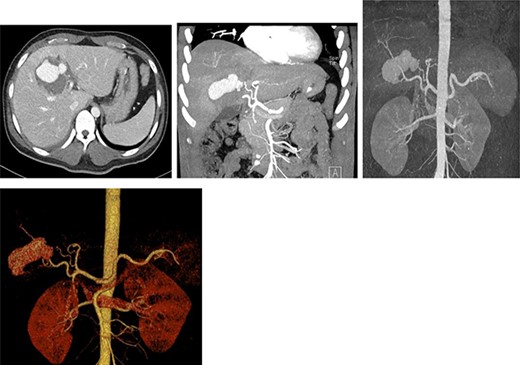

Resuscitation was carried on with 2 l of normal saline and two PRBC units to stabilize the patient. The computed tomography (CT) scan identified Grade 4 liver injury with hemoperitoneum (Fig. 2). Subsequently, the multiple bone fractures underwent surgical fixation, and post-operatively, he was hemodynamically stable. On the fifth day after admission, repeated CT scan demonstrated the liver injury with no evidence of hepatic pseudoaneurysm (Fig. 3). The patient remained stable with tolerated feeding with no abdominal pain or distension. On the Day 17, he developed abdominal pain mainly in the epigastrium, which was associated with nausea and deep epigastric tenderness. Abdominal ultrasound (US) (Fig. 4) and CT scan (Fig. 5) revealed complex, large intraparenchymal hepatic pseudoaneurysm (measuring about 58 × 41 × 30 mm) related to the left hepatic artery Segment 4 branch with surrounding hematoma located mainly at segment 4B/A ,and there was another tiny pseudoaneurysm seen at Segment 4A. Selective angiography confirmed the diagnosis of pseudoaneurysm with multiple blood supplies from Segment IV and Segment II.

Contrast-enhanced CT scan revealing a right hepatic artery pseudoaneurysm in the right lobe of the liver.